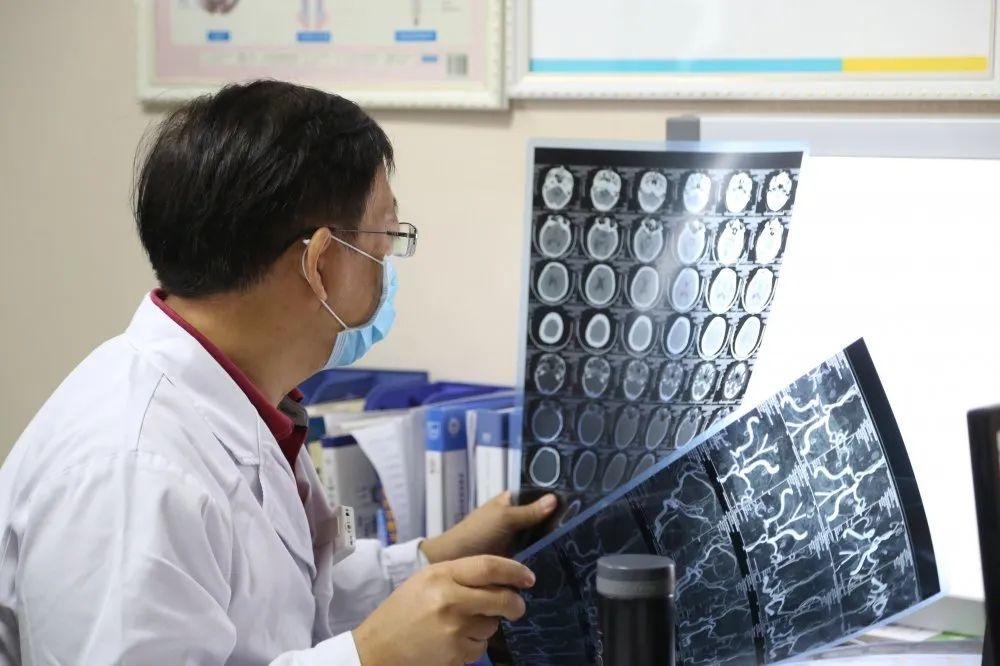

来到我院自述“除了手麻,还感觉全身无力”。这一症状让经验丰富的医生脑中闪过了一个念头:“会不会是神经损伤?”经神经内科会诊为其完善头颅MR检查后,果然发现有颅内多发梗塞灶,立刻对其进行了对症治疗。

好在小张来院及时,目前经过系统治疗已康复出院。指出,脑梗急救不仅要“快”,更要送“对”。虽说脑梗症状跟颈椎病很像,但其实颅内多发梗塞灶的疼痛,也有一些特点,如伴有肢体无力、口角歪斜、口齿不清等症状,一定要通过影像学检查明确病因,千万不能简单地对号入座。